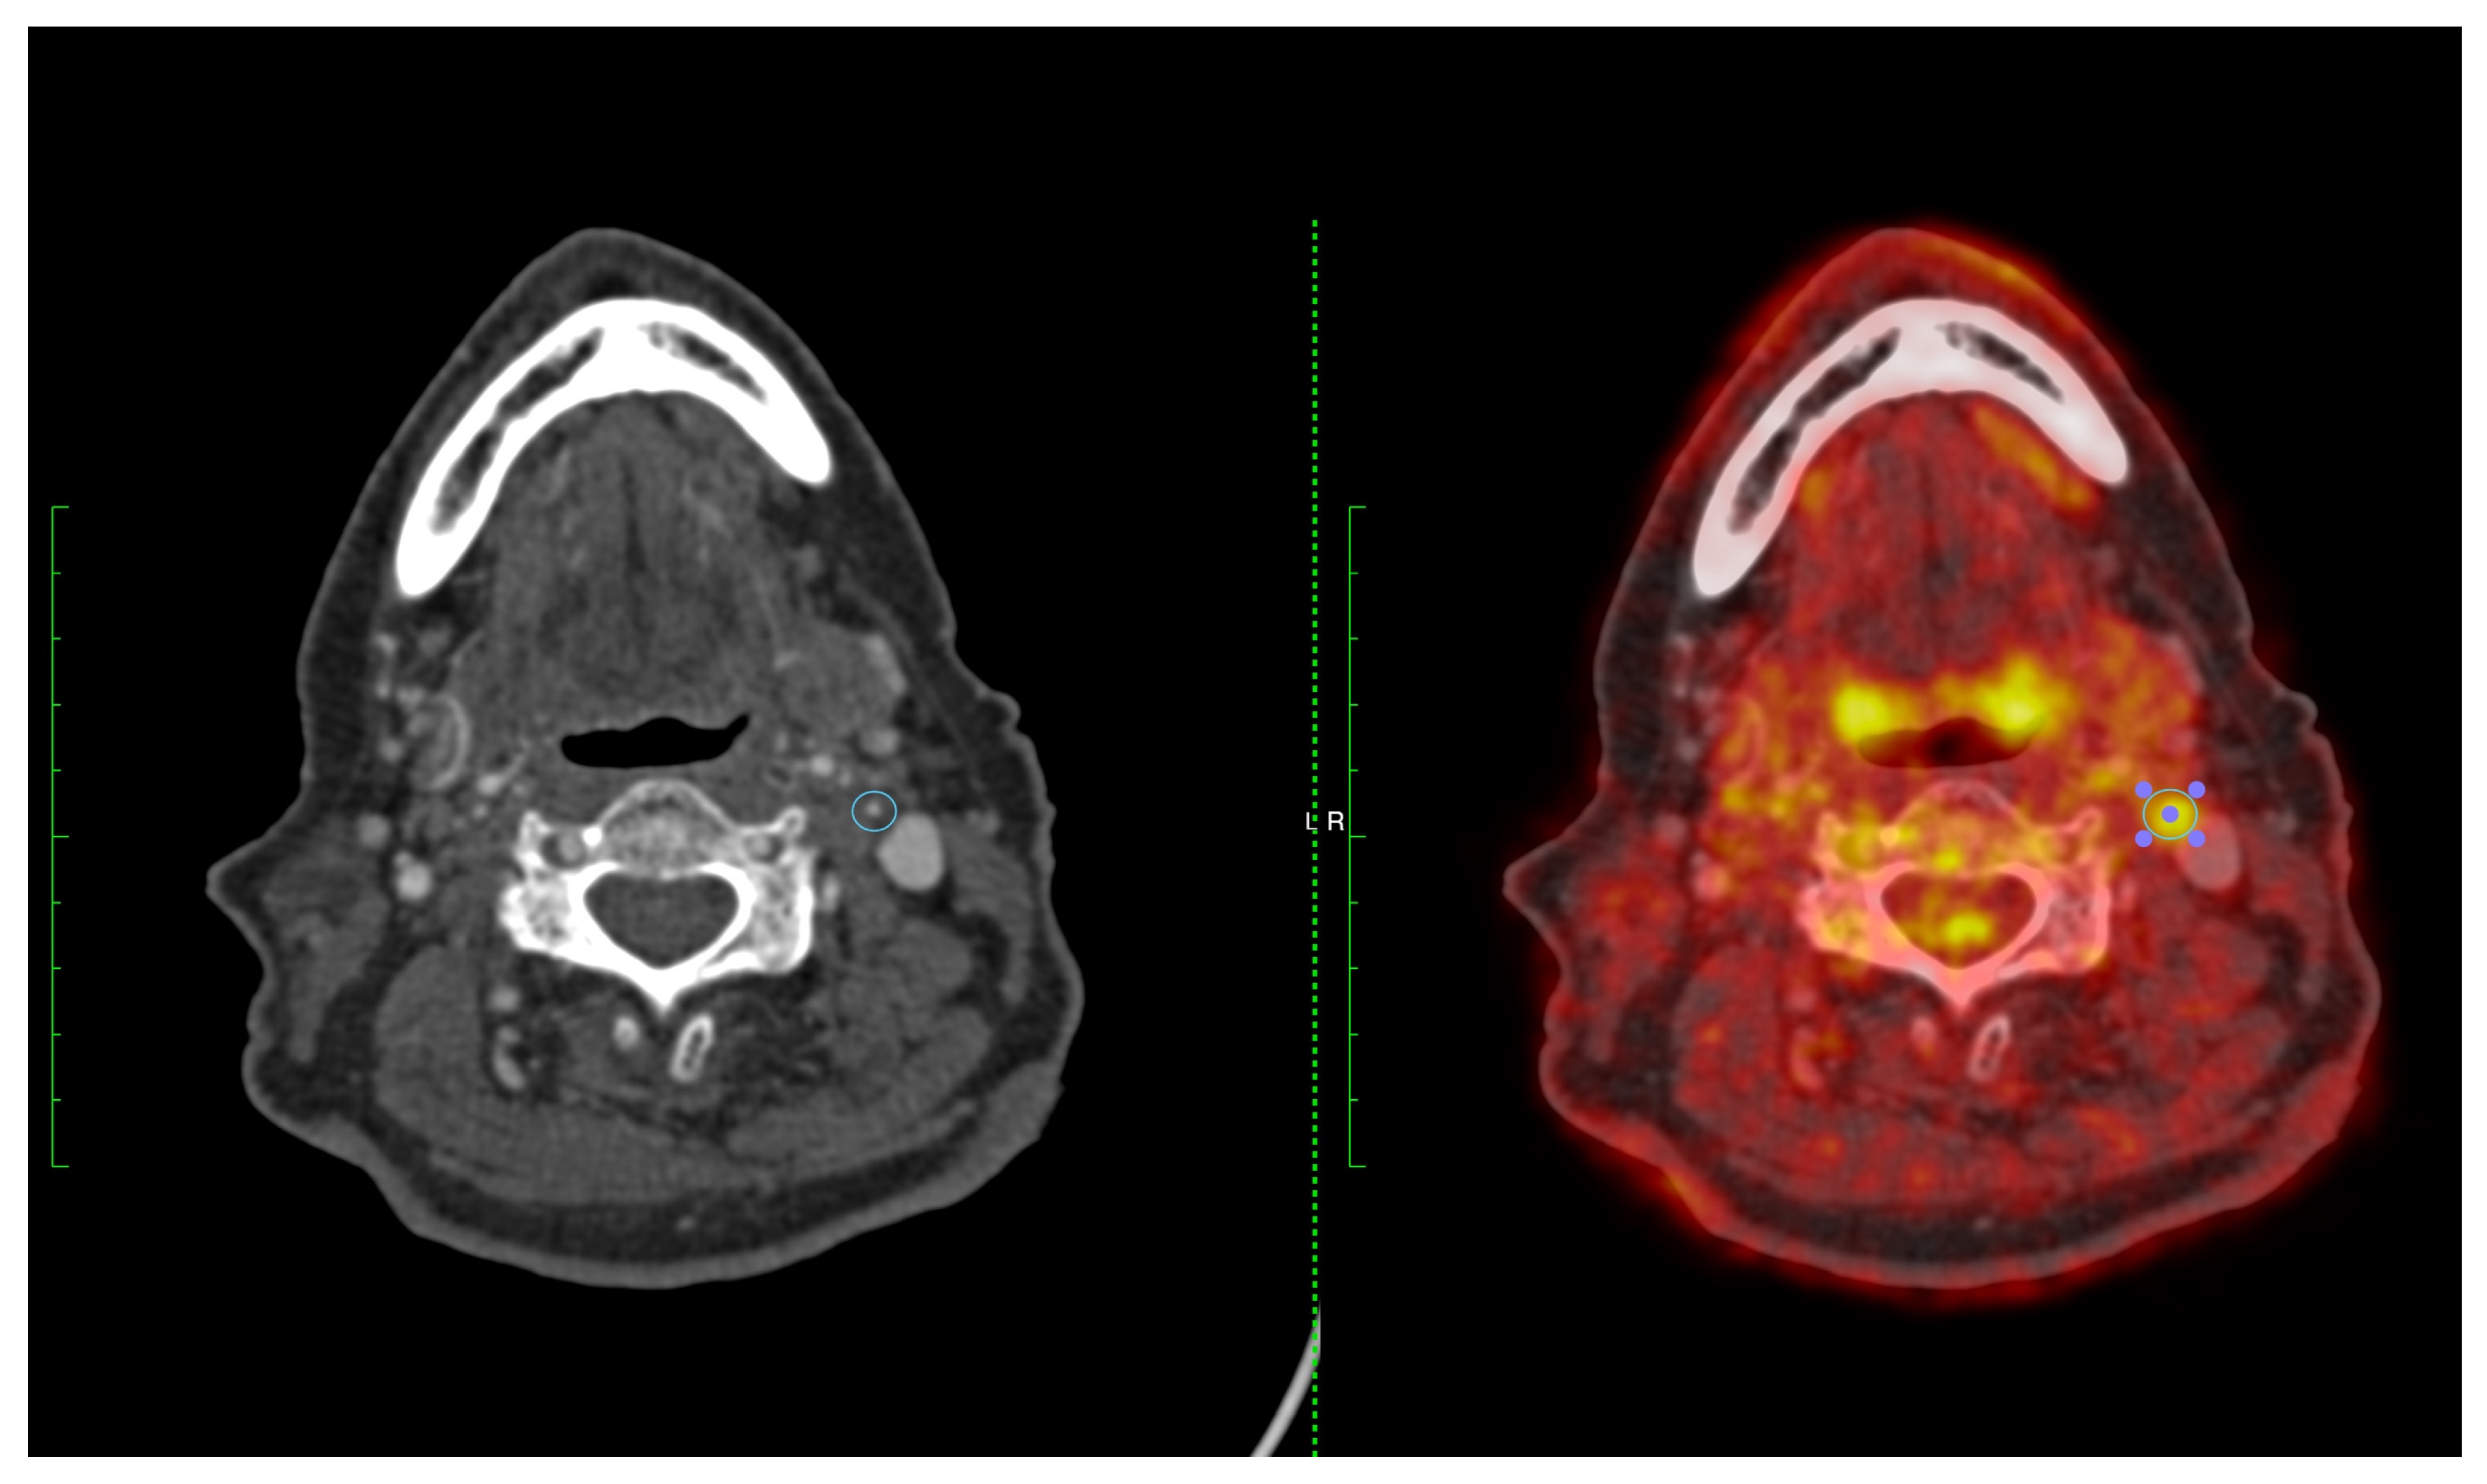

Figure 4.

A 74-year-old man with expressive dysphasia and a left frontal infarct. CT angiography demonstrated a severe left ICA stenosis measuring 70–80% (left panel). FDG-PET showed high FDG uptake in the left ICA 4.05 g/L (right panel) (SCAIL score 5).